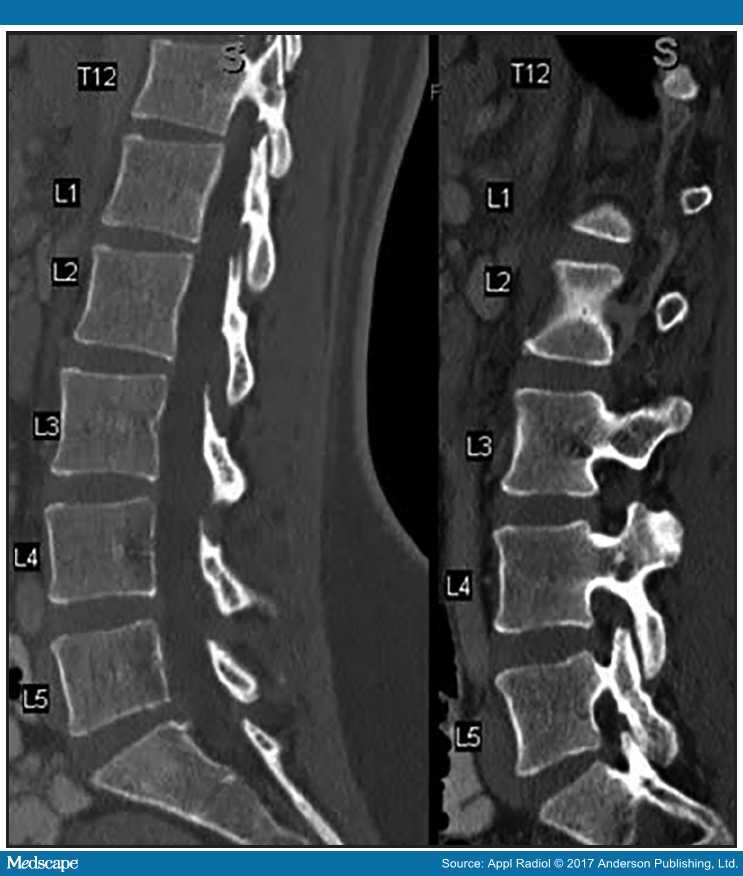

Annual listhesis picture This image representes annual listhesis.